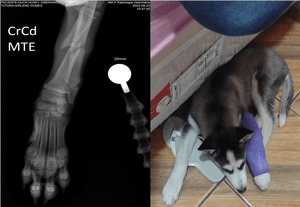

Boa tarde! Filhote doado estava com pata muito inchada e quase fratura exposta, levei ao veterinario, paguei consulta, raio x e medicamento pra dor e pra não inflamar.  Fiz diversos orçamentos mas não consigo pagar o valor total das cirugias, raios x, anestesia, internação e remédios. Peço ajuda pra não ter que amputar. Serão necessárias 2 cirurgias, uma pra colocar placa e pino e outra pra retirar.